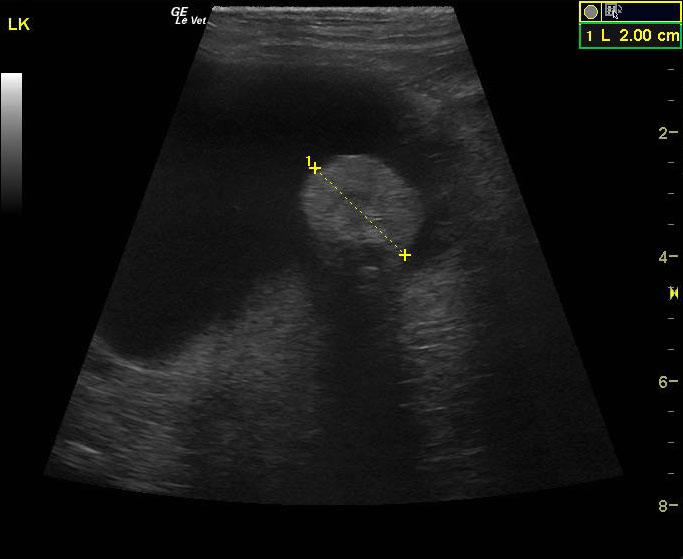

A 15 year old spayed female DMH cat was presented for progressive disease over a 6-8 month period, characterized by poor coat quality, decreased mobility, reduced activity, and pruritic skin lesions that have not responded to antibiotics and use of an E-collar. Abnormalities on physical examination were alopecia, hyperpigmentation, and thinning of the skin of the ventrum, and a non-healing, plaque-like, superficial skin lesion on the cranial aspect of the left stifle and accessory pad of the left carpus. Skin biopsies were scheduled. On urinalysis an inappropriate SG and proteinuria was present with a urine protein: creatinine ratio of 0.3. Abnormalities on serum biochemistry included hypercalcemia and hyperproteinemia. Radiographs showed arthritis of elbow, LS junction, and hips, as well as a mass in the region of the left kidney.